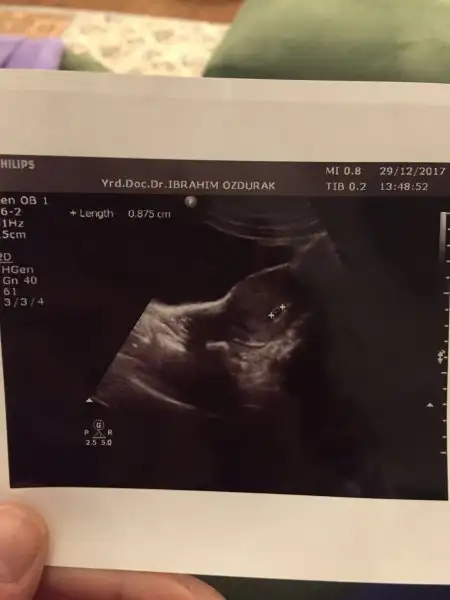

Yükleyebildim mi bilmiyorum ultrason görüntüsünü ilk kontrolüme bugün gittim. Nihayet gidebildim:) Keseyi gördüm kalp atışlarıda görülüyor dedi doktor ama dinletmedi. Ultrasondan oldum olası bişey anlamam.doktordan geldiğimden beri kağıtla bakışıp duruyorum:anneadayı::KK200:

Ben bebeği görüyorummmm. Ay miniklerimiz yaaa insan tuhaf oluyor :)